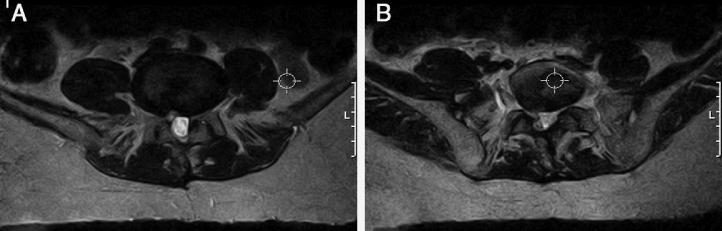

Lumbar stenosis is an increasingly common pathological condition that is becoming more frequent with increasing mean life expectancy, with high costs for society. It has many causes, among which degenerative, neoplastic and traumatic causes stand out. Most of the patients respond well to conservative therapy. Surgical treatment is reserved for patients who present symptoms after implementation of conservative measures. Here, a case of severe stenosis of the lumbar spine at several levels, in a female patient with pathological and surgical antecedents in the lumbar spine, is presented. The patient underwent two different decompression techniques within the same operation.